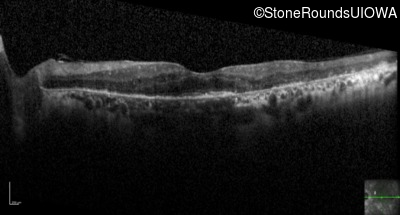

Optical Coherence Tomography - Left - 20/70 +1

Exemplar / OCT Stack